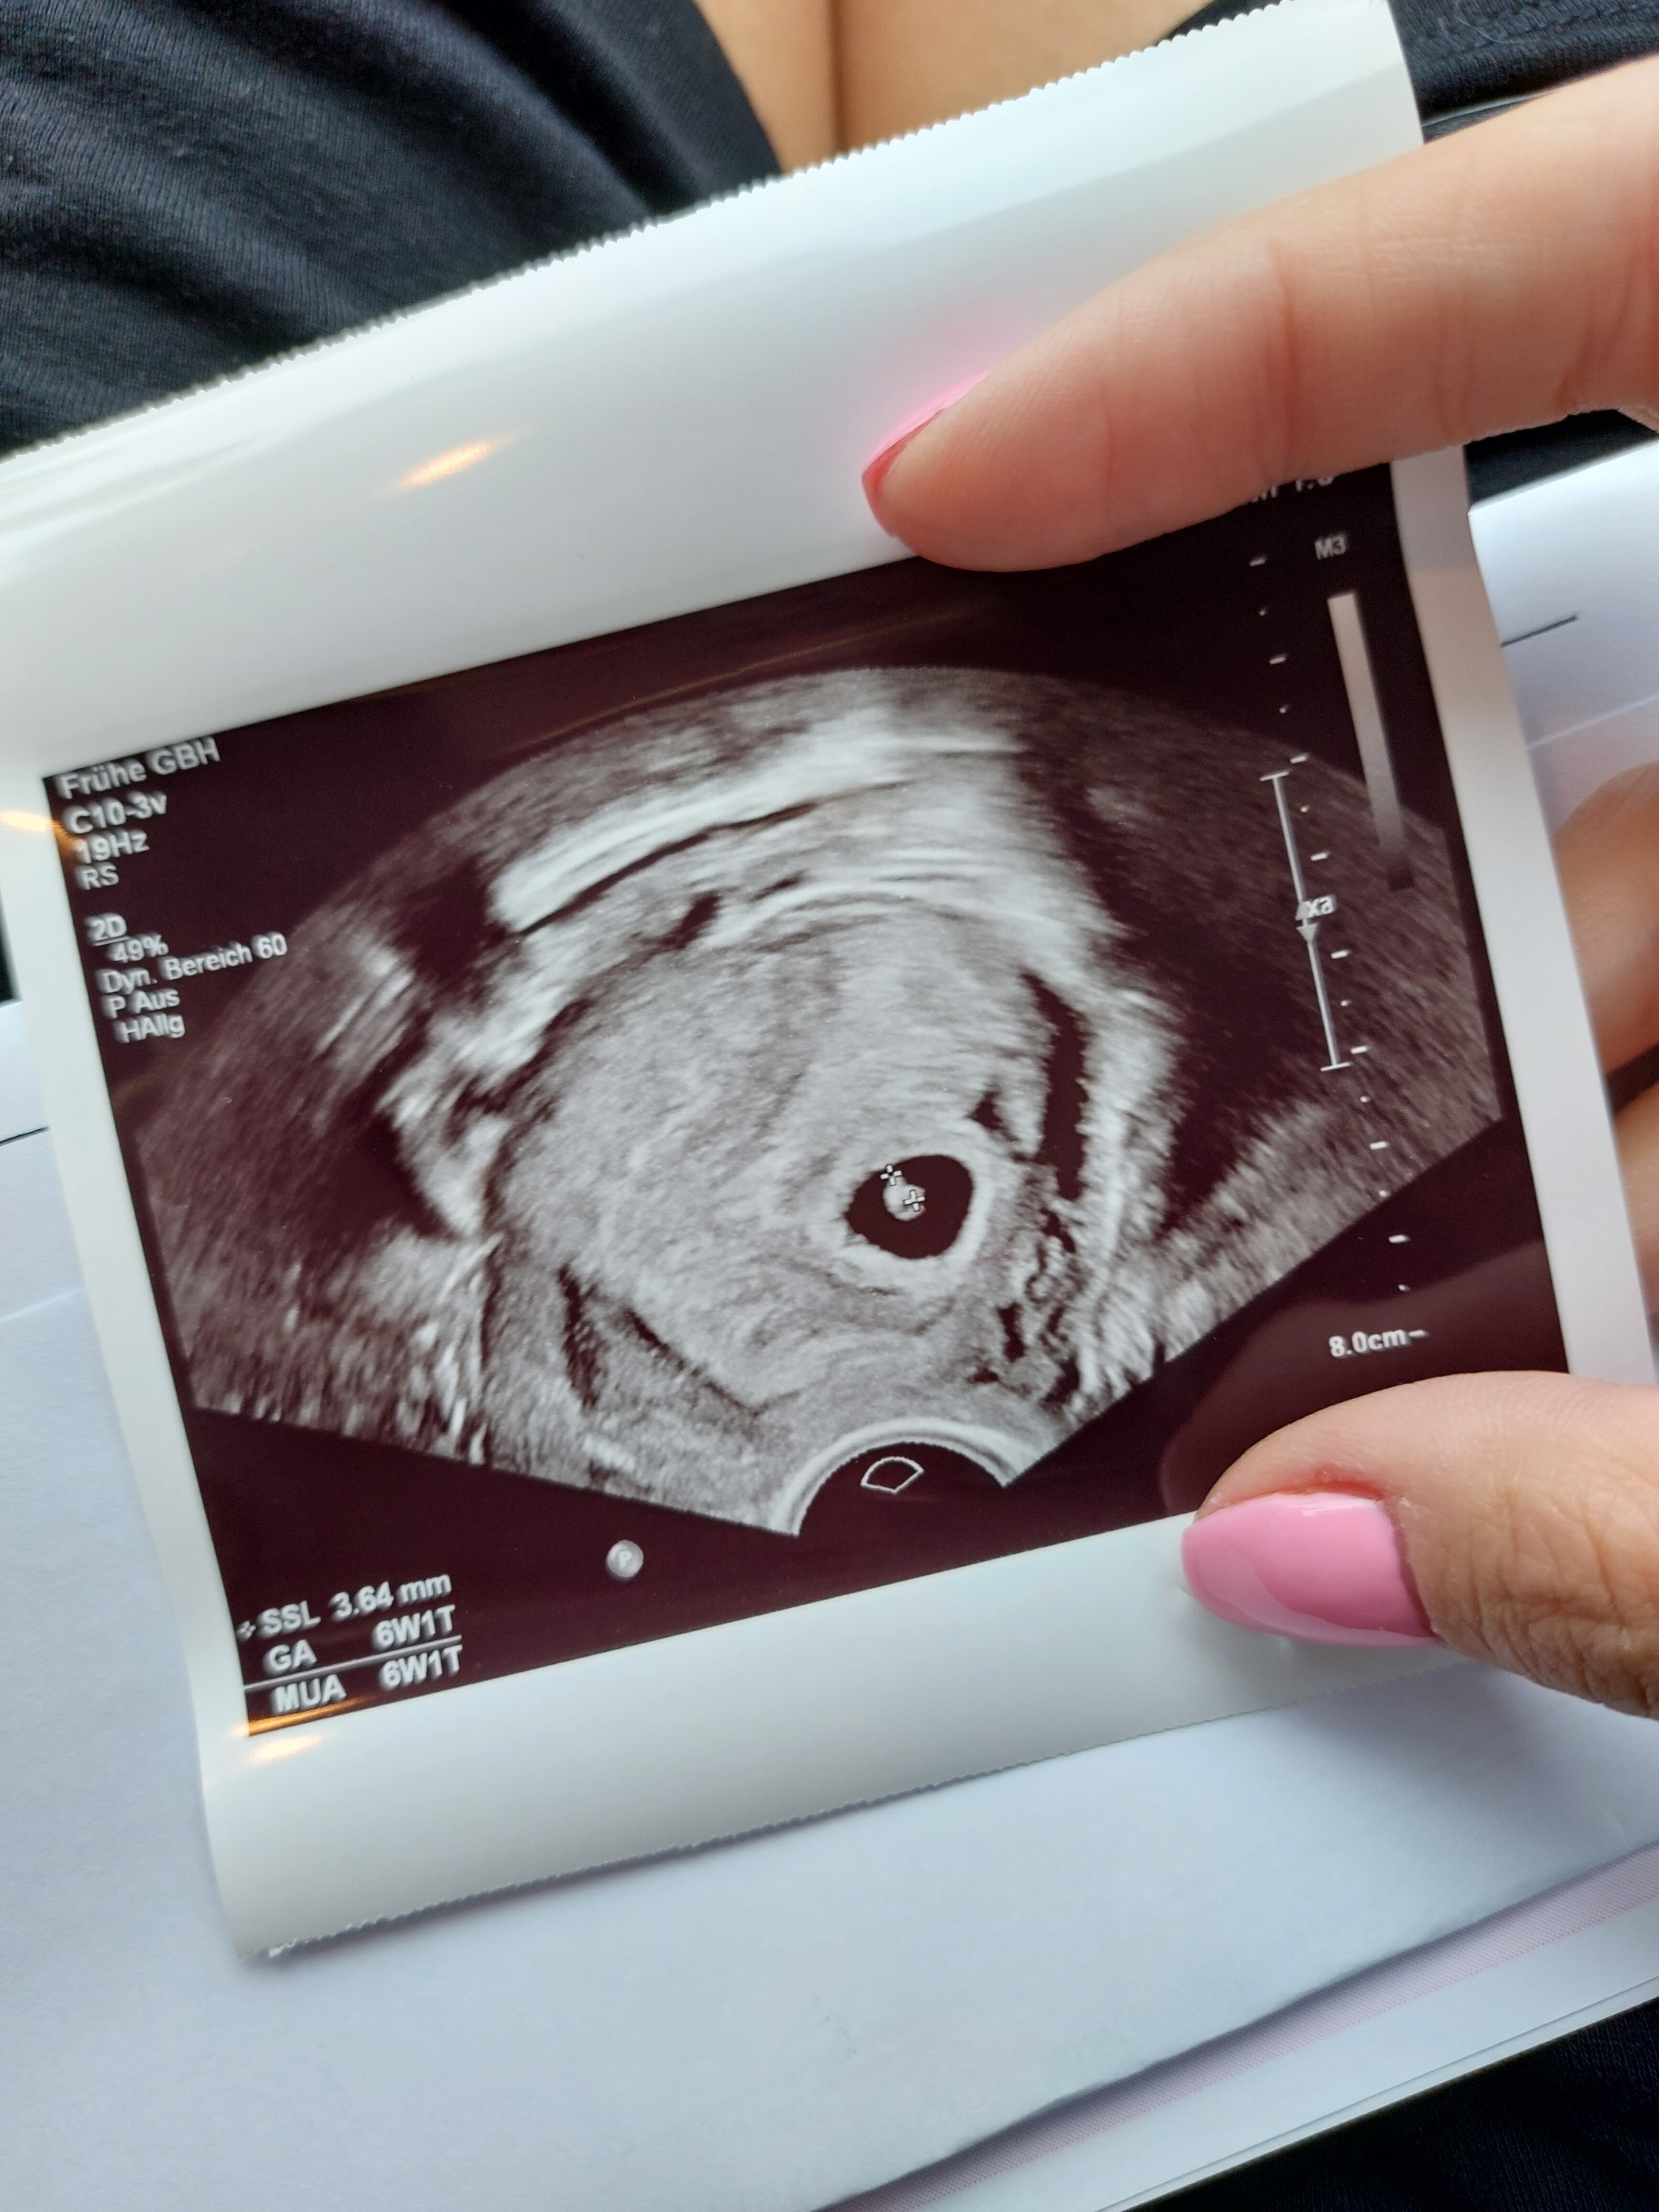

Na wizycie u ginekologa 6+1, i zarodek 😍

To było 10dni temu, w najbliższy poniedziałek kolejne usg, oczekujemy serduszka.